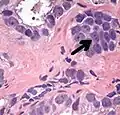

- Intraductal carcinoma of the prostate with an infiltrative growth pattern may be morphologically difficult to distinguish from invasive cancer. One focus shows comedonecrosis (arrow), morphologically suggesting Gleason pattern 5 invasive carcinoma (a haematoxylin and eosin, b CK5/6)[19]

- Intraductal carcinoma of the prostate with very patchy basal cells identified by immunohistochemistry. At least some of the glands lacking basal cell immunoreactivity represent intraductal rather than invasive carcinoma (a haematoxylin and eosin, b CK 5/6)[19]